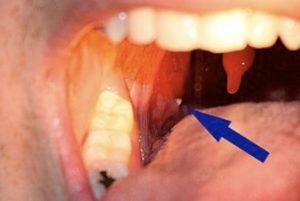

Tonsil stones, or tonsilloliths, are small calcified formations that develop in the crypts of the tonsils, where food particles, dead cells, and bacteria can get trapped. While often harmless, they can cause persistent discomfort, bad breath, and a feeling of a foreign object in the throat. Some people may also experience difficulty swallowing, throat irritation, recurrent tonsillitis, or persistent coughing.

Small stones may dislodge naturally while eating or coughing, or can be removed with saltwater rinses or a water irrigator. For larger or recurrent stones, a specialist may need to remove them safely. In severe cases, tonsillectomy may be considered.